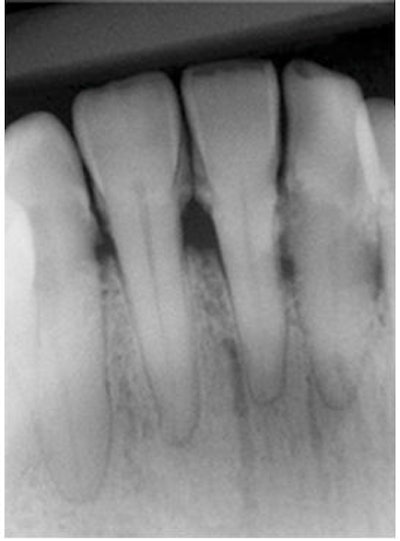

A similar type of evaluation can be done with periodontal disease using XDR software by Cyber Nedical Imaging.

On the left below is the initial radiograph, and on the right is the radiograph after enhancing the image.